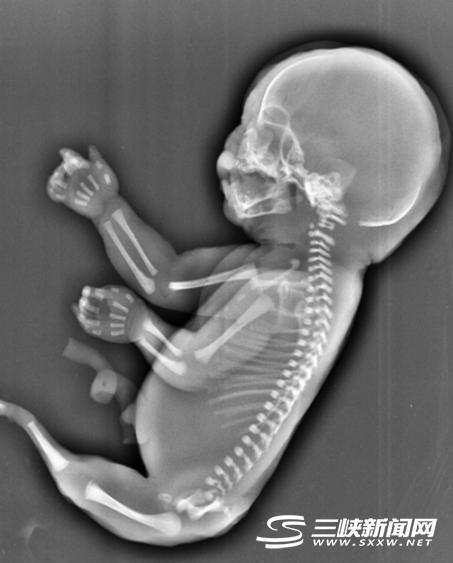

年輕媽媽懷“人魚寶寶” 胎兒無腿有尾巴

湖北省宜昌市懷孕25周、23歲的吳女士(化姓)前往市婦幼保健院孕檢,發(fā)現(xiàn)胎兒下肢無雙腿,只有一條類似于美人魚的“尾巴”。昨日,記者從宜昌市婦幼保健院獲悉,這是一種十分罕見的畸形,吳女士已終止妊娠。

吳女士當時經(jīng)超聲檢查發(fā)現(xiàn),孕婦宮腔內(nèi)未見羊水暗區(qū),借助胎兒骨骼影像順序連續(xù)掃查,發(fā)現(xiàn)胎兒頭顱、胸腔、雙上肢,也可以看到一個跳動的心臟。但下肢只找到一條股骨,未見雙腿、膀胱,只有一側(cè)發(fā)育不良的腎臟。

美人魚綜合癥是一種極其罕見的先天性下肢畸形疾病,6萬-10萬人中才有1例,患病的新生兒出生后只能夠存活幾個小時。 關(guān)于其病因至今仍是個謎,但醫(yī)學(xué)專家認為可能和遺傳基因有關(guān)。已知的美人魚綜合癥幸存者只有2人,存活率極低。

美國10歲女孩夏伊洛·皮平因先天性疾病而生來雙腿粘合在一起,而且膀胱、子宮、大腸、大部分腎臟等器官缺失,被稱為“美人魚”女孩。她已接受過150多次手術(shù),可是最終還是沒有成功的活下來。